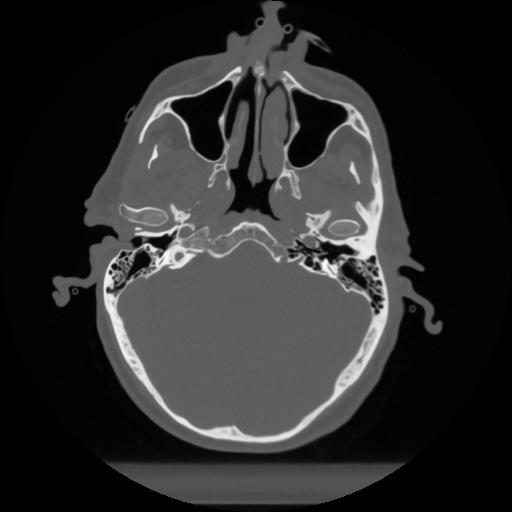

12 P.BLANDAS,,Vol,0.5,P.BLANDAS,,